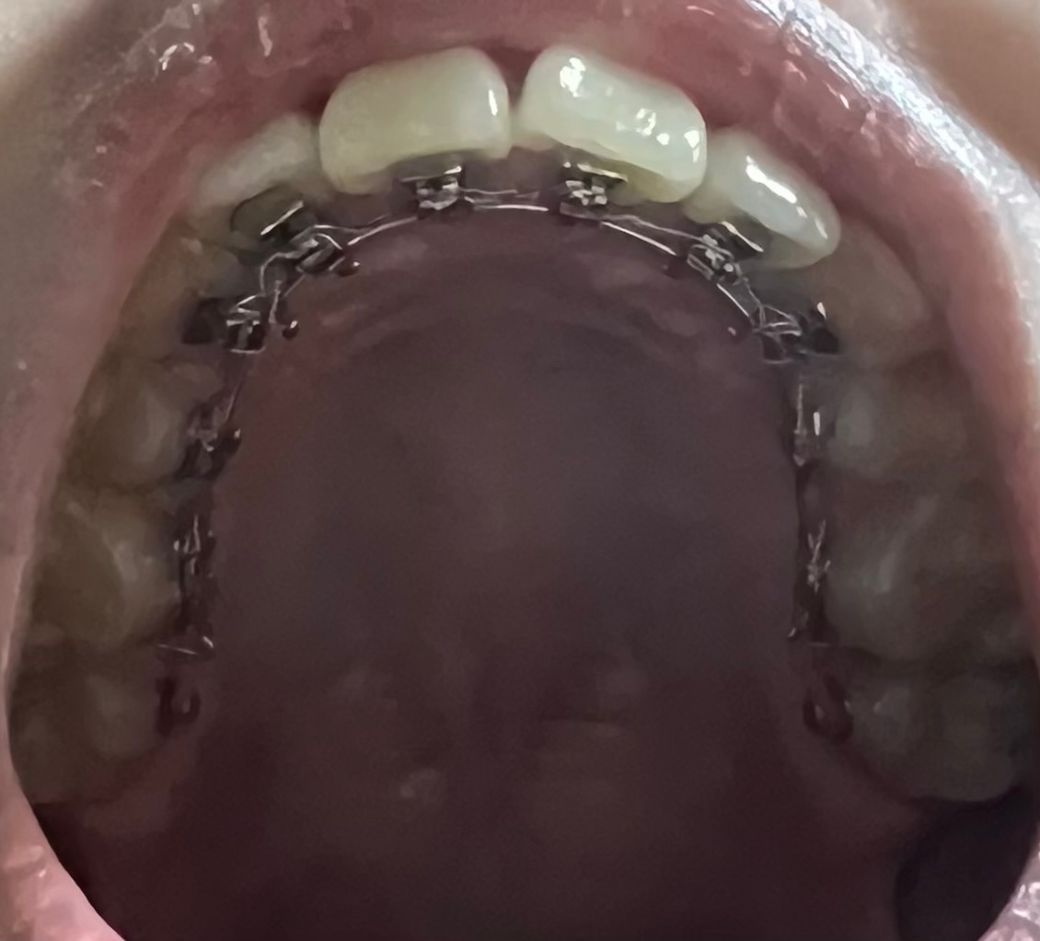

치아 교정이 마무리 단계에 들어서서 교합 고무줄을 끼는 중인데, 이 정도면 앞니 부분이 완전히 고르게 펴지지 않은 건지 잘 모르겠어요

아랫니는 깔끔하고 예쁜 상태인데 윗니의 앞니 부분이 정교하게 들어맞지 않은 거 같아서요.설측 교정 중이라 이 정도의 차이는 세세하게 맞추지 못하는 걸까요? 담당 선생님께 설명을 드리고 이거 때문에 더욱 앞니 부분에 음식물이 잘 껴있는 거 같다 말씀을 드려도 돌아오는 대답은 원래 교정 중에는 치아가 흔들려서 음식물이 잘 끼는 거라는 답 뿐이라... 제가 너무 완벽을 원하는 건지 고민입니다...

치아 교정의 경우 치열이 고르게 되는것도 중요하지만 교합가 함께 맞춰야 되는거라서 무조건 가지런하게만 한다고 해서 교정이 잘된건 아닙니다. 사진상으로는 잘된거 같습니다.

개인적으로는 전체적인 치열은 괜찮으나 사진상 왼쪽 맨 앞니의 치축이 약간 입천장 쪽으로 기울어서 전치부 절단연의 라인이 약간 불일치해보입니다.